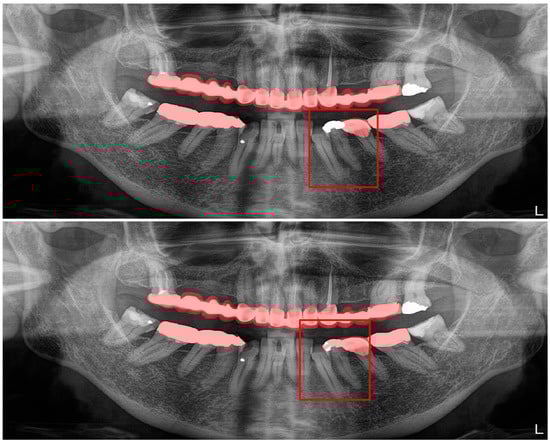

Figure 2.

Automatic segmentation of the teeth. Manual segmentation (upper image) and automatic segmentation (lower image) can be seen above. Each tooth has a unique label according to FDI World Dental Federation notation.